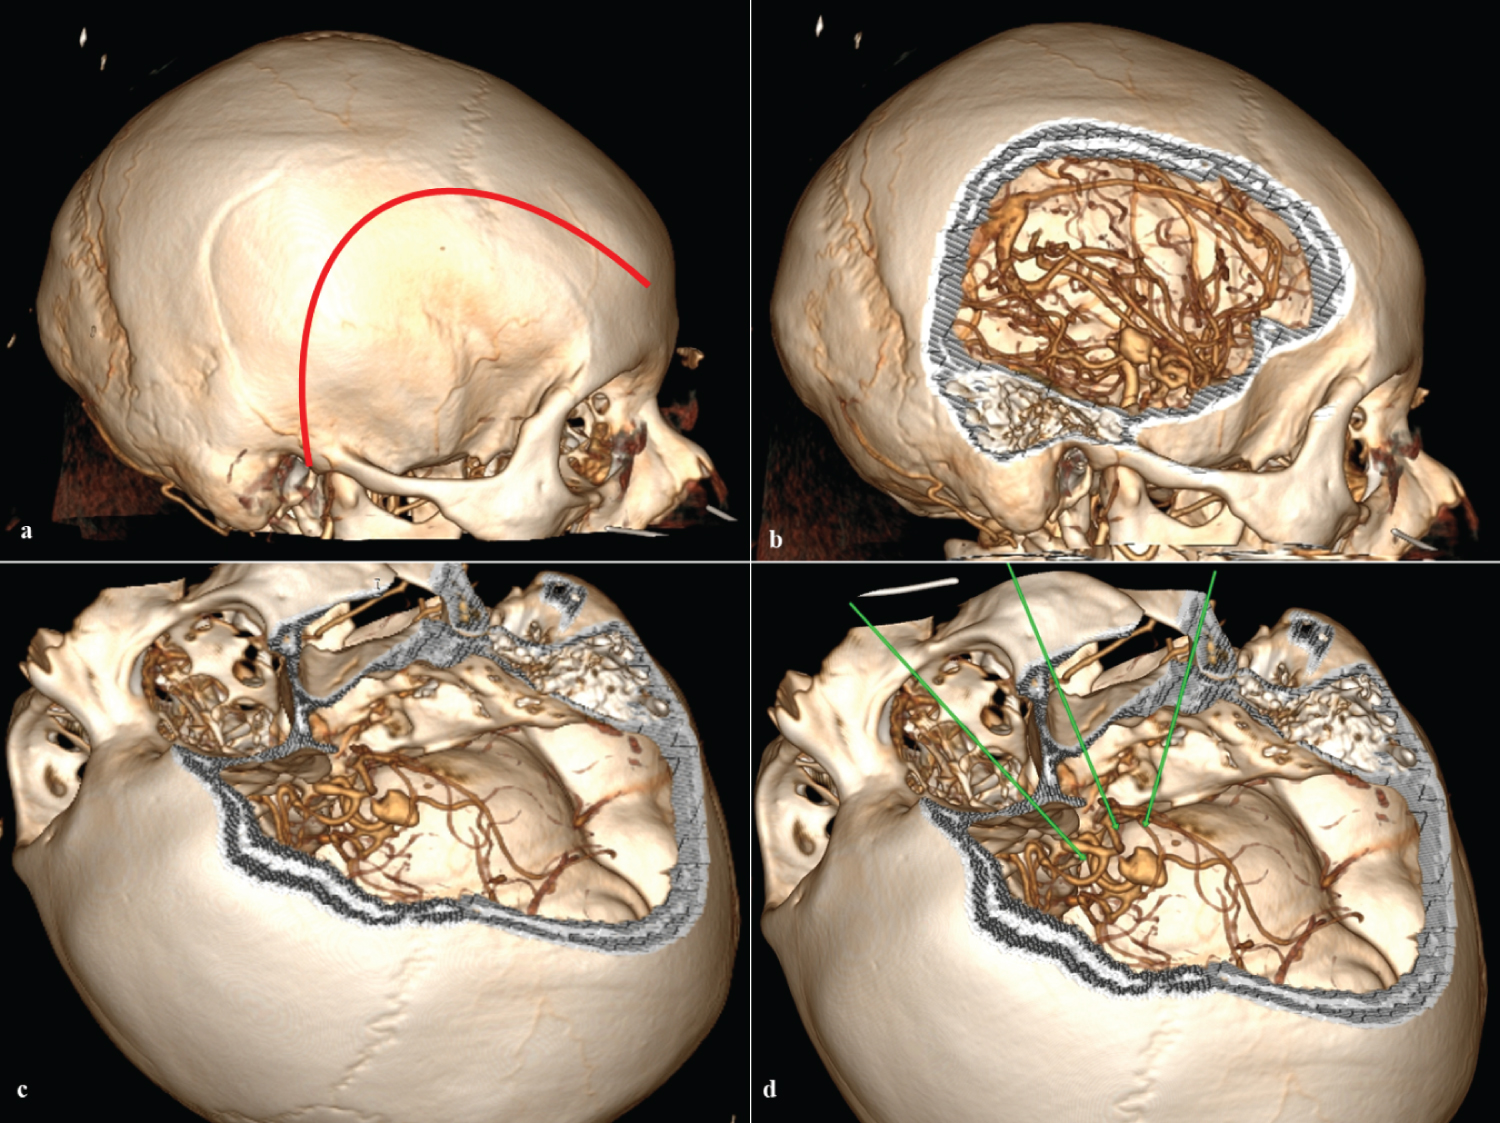

A right fronto-temporo-zygomatic craniotomy was performed (Figure 2), wide dissection of the Silvian fissure, proximal control with temporal clipping of the basilar artery, and identification and clipping of the aneurysm. We corroborated the permeability of the posterior brain and collaterals with fluorescein and reviewed with the endoscope the area that did not allow us to observe the microscope and rule out the possibility of an inadvertent clipping of collaterals (Figure 3).

Figure 2: 3D tomography. a) Frontotemporal skin incision (red line); b) Right lateral view of right frontotemporal craniotomy; c) Surgical position and craniotomy with zygomatic frontotemporal enlargement; d) Surgical position and access corridors to the aneurysm (green line). View Figure 2